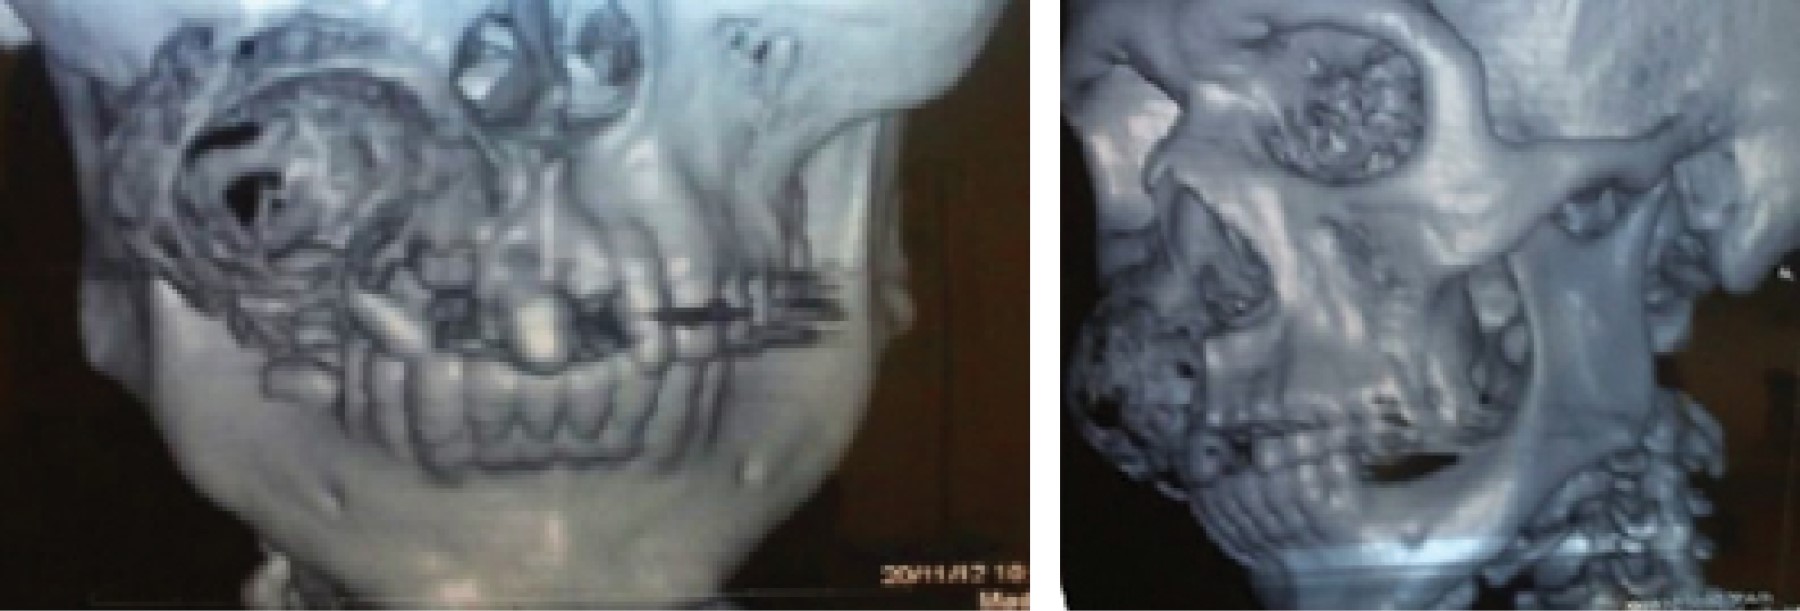

Odontogenic myxofibroma, case report with 5 years of follow-up.

Odontogenic myxoma is a slow-growing locally invasive intraosseous lesion with defined microscopic appearance. Radiographic appearance, is described as multilocular radiolucent lesion, which is reported in scientific literature as "honeycomb" or "soap bubbles" appearance most of the time; it exhibits dental displacement and cortical expansion. Histopathologically, stellate and spindle cells with cytoplasmic processes are observed in a mucoid or myxoid substance, with or without collagen; when it contains large amounts of mature cellular fibrous tissue, it is called myxofibroma. The present article presents the case of a 38 year old male, who attended the General Hospital in Uruapan, Michoacán due to an increased volume in the right maxillary region. Incisional biopsy was performed and the histopathological diagnosis of odontogenic myxofibroma was emitted. 33.6% of cases occur in the maxilla with a uniform distribution throughout the areas, and can erode the maxillary sinus. It has a recurrence rate of 10 to 33%, therefore ideal treatment is bloc resection leaving safety margins.

Figure 1

Figure 2

Figure 3

Figure 4